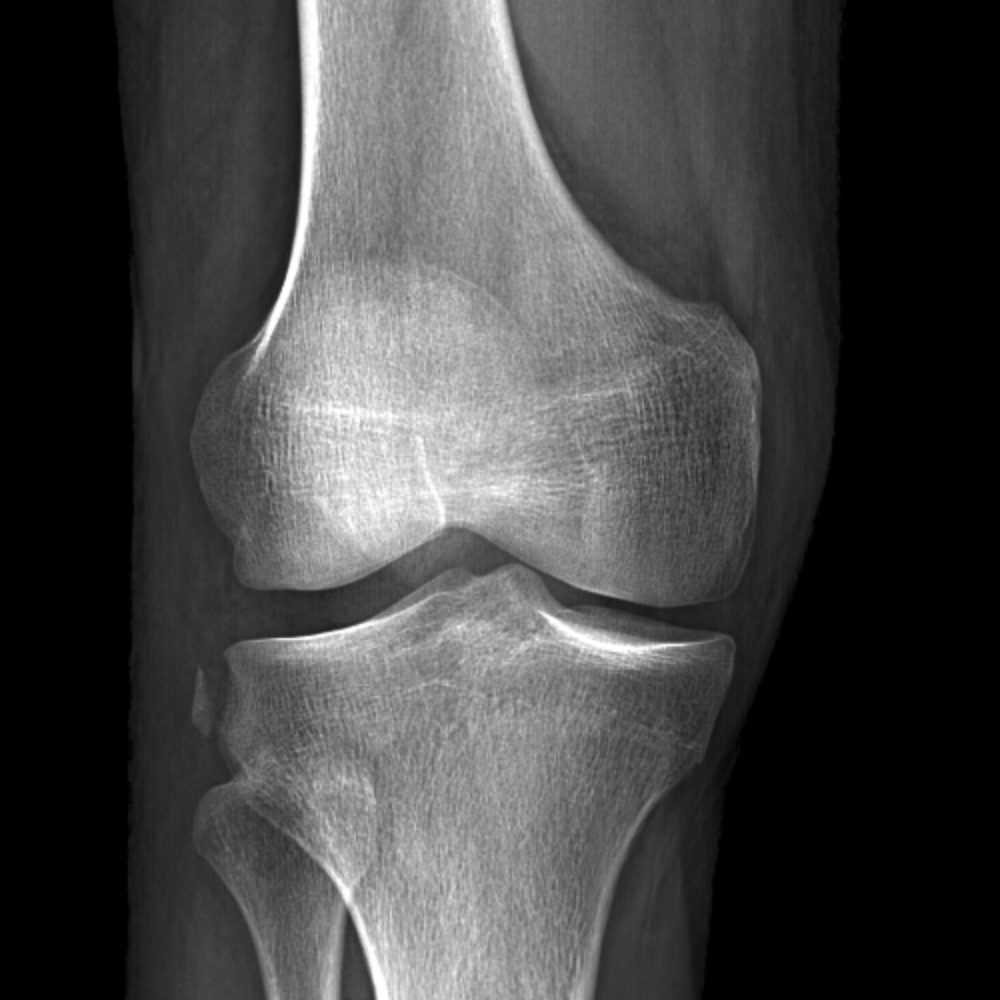

Avulsion fracture (small) of the lateral surface of the lateral tibial condyle. Segond fractures have a high association with acl ruptures, being present in 75% to 100% of cases.

A segond fracture is an avulsion fracture located in the lateral aspect of the tibial plateau of the knee.6. Segond fracture is an avulsion fracture of the knee that involves the lateral aspect of the tibial plateau and is very frequently (~75% of cases) associated with disruption of the anterior cruciate ligament. All will feature in our upcoming emergency radiology course.

A segond fracture is an avulsion fracture located in the lateral aspect of the tibial plateau of the knee.6. The mechanism of injury is internal rotation and varus stress. Tibial plateau on lateral aspect shows subtle ill definition and distal tibia below the plateau is unremarkable with no definite avulsion fragment away from the bone even on tunnel view. Segond fracture is an avulsion fracture of the knee that involves the lateral aspect of the tibial plateau and is very frequently (~75% of cases) associated with disruption of the anterior cruciate ligament. Use of ct and mr imaging improves assessment; Segond fracture = avulsion of the anterolateral aspect of the lateral tibial plateau. Varney jb, reverse segond fracture without pcl injury. A segond fracture is an avulsion fracture located in the lateral aspect of the tibial plateau of the knee.6. Ct scan 3d reconstruction shows reverse segond fracture (yellow arrow). The segond fracture is a type of avulsion fracture (soft tissue structures tearing off bits of their bony attachment) of segond fracture — se·gond fracture (sə gawґ) [paul ferdinand segond, french. Segond fracture is an eponym that refers to an avulsion fracture of the anterolateral margin of the proximal. A rare, mirror image of the segond fracture has also been described. A small avulsion that reflects major ligamentous damage. Avulsion fracture of proximal lateral tibia. This is an avulsion fracture of the lateral tibial condyle immediately beyond the inability to flex a knee to 90°. Not necessarily pathognomonic of anterior cruciate ligament injury in the. On the radiograph you could easily miss the segond fracture (red arrow).